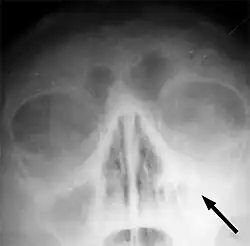

Brak przejrzystości lewej zatoki szczękowej oznacza obecność płynu (ropy) lub obrzęk błony śluzowej